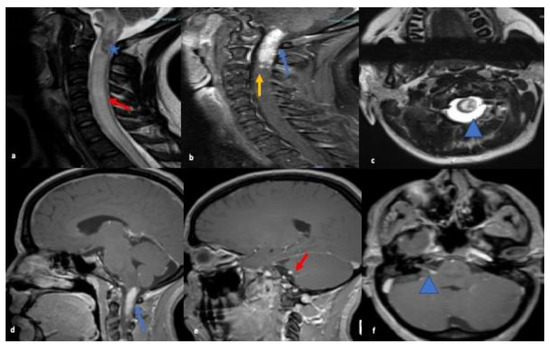

The serum autoimmune and infectious work up were unremarkable. MRI orbits showed soft tissue thickening and enhancement in the left orbit with enlarged extraocular muscles, enlarged lacrimal gland and osseous involvement of the sphenoid bone (refer Figure 2). Differential at that time included cellulitis and lymphoproliferative disorder. She was started on oral antibiotics followed by left orbitotomy and excision of the mass. Biopsy of the mass revealed granulomas and the patient was diagnosed with orbital sarcoidosis. CT chest/abdomen/pelvis were without evidence of malignancy or systemic sarcoid. No lumbar puncture was performed as diagnosis was confirmed on biopsy.

Figure 2.

MRI orbit T2 fat-suppressed coronal images reveals nodular thickening of the left lacrimal gland (red arrow; (a)), superior and lateral recti muscles (yellow arrow; (a)). T1-weighted post contrast axial (b) and coronal images (c) showing corresponding enhancement within muscles, lacrimal gland and in intraconal orbits surrounding the globe (blue arrowhead).T1 weighted post contrast coronal image (d) reveals enhancing nodule in the greater wing of left sphenoid concerning for osseous involvement (blue arrow).

She was started on oral prednisolone 10 mg daily, methotrexate 10 mg weekly; later increased to 15 mg weekly maintenance dosage. On her follow up visit, disease activity improved. The diplopia had resolved and the patient’s vision returned to baseline (20/20) bilaterally. She was continued on her medications with a reduction in methotrexate dose to 12.5 mg weekly and is being gradually tapered off of steroids (refer Table 1).

NS can affect the neurological system in various ways. One of these is cranial nerve involvement. Any of the cranial nerves can be involved in NS [11] but the most frequently reported is cranial nerve VII [1]. The first case in our series presented with lower motor neuron VII nerve palsy and VIII nerve involvement leading to a misdiagnosis of Bell’s palsy and ear infection. Multiple cranial nerve involvement, lesion within the brainstem and intramedullary lesions within the upper cervical spinal cord were seen on MRI were present in this case of NS. Despite treatment with steroids, the patient did not initially show improvement, complicating the case even further. The second case, initially diagnosed as orbital cellulitis, also demonstrated multiple cranial nerve involvement with ophthalmoplegia secondary to infiltration of the extraocular muscles due to granulomatous masses. The patient experienced loss of vision in the left eye due to surrounding inflammatory changes and mass effect. A subsequent biopsy confirmed the diagnosis of orbital sarcoidosis. Hence, cranial nerve involvement with other CNS lesions should raise suspicion for NS and treatment with steroids may not show a significant response initially.

The second case, initially diagnosed as orbital cellulitis, had second cranial nerve involvement with marked loss of vision in the left eye. There was also infiltration of extraocular muscles with pain upon eye movements and ophthalmoplegia due to granulomatous mass. Orbital sarcoid manifestations include thickening and enhancement of the intra-orbital and intracranial optic nerve and chiasm, optic atrophy and orbital masses. These are often mistaken as pseudotumor, glioma, meningioma of the optic nerve sheath, MS, or infectious etiology such as syphilis, lymphogranuloma venereum, leprosy, tularemia, torulosis, histoplasmosis, blastomycosis, and coccidioidomycosis [25,26,27,28,29]. Fast spin-echo fat suppressed axial and coronal T2, and T1 axial and coronal fat-suppressed contrast-enhanced MRI images are considered to be the standard protocol to investigate for intra-orbital or optic nerve disorders [30].